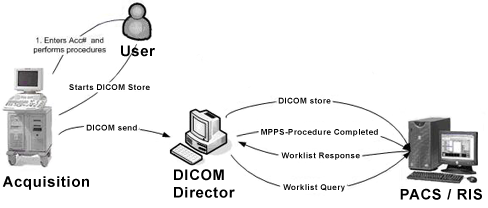

Лазерная камера сетевая для печати изображений на пленке стандарт dicom